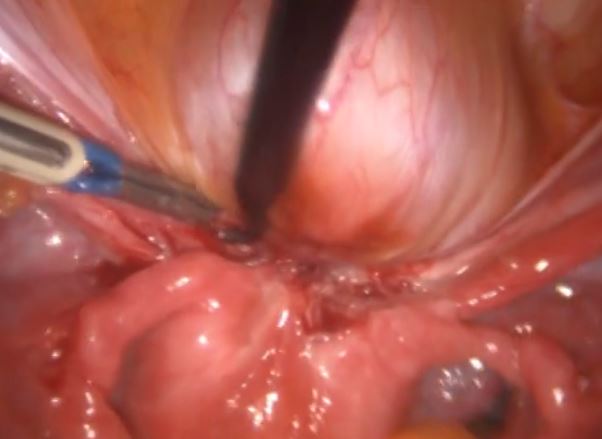

Endometriose na bexiga firmemente aderida ao útero evidenciada pela laparoscopia.